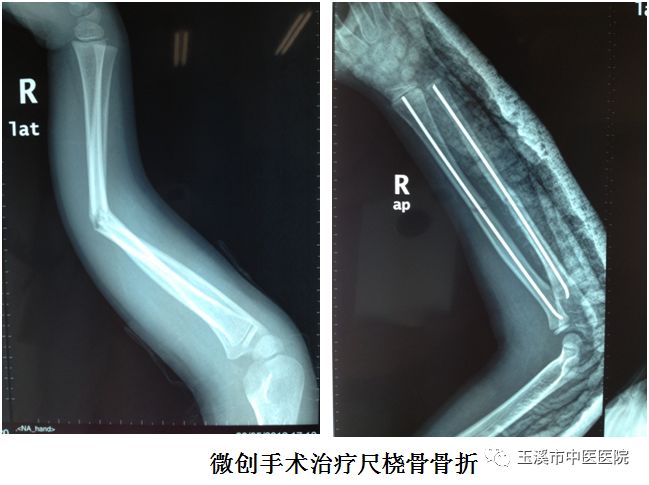

全省地州級(jí)首家專門(mén)診治兒童骨科疾患的??朴裣兄嗅t(yī)醫(yī)院骨傷科于2011年創(chuàng)建成為“國(guó)家級(jí)重點(diǎn)專科”;2009年骨傷科開(kāi)設(shè)小兒骨科病房;2014年成立小兒骨科病區(qū);2018年6月1日正式成立小兒骨科,至此成為全省地州級(jí)首家專門(mén)診治兒童骨科疾患的???。

兒童骨折、脫位、創(chuàng)傷、感染、骨病、骨腫瘤、先天性畸形及發(fā)育異常等常見(jiàn)疾患。